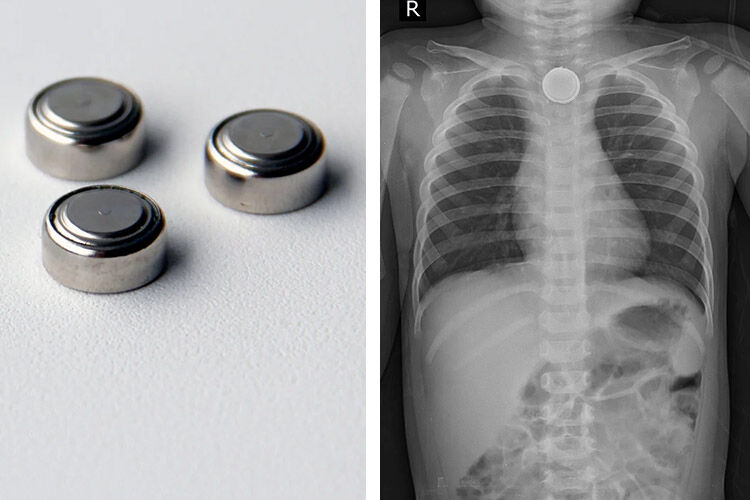

Are Button Batteries Dangerous . parents and caregivers need to be aware of the risk posed by button batteries and lithium coin batteries in their home. button batteries can cause serious burns and complications if swallowed, placed in the ear or nose. Learn how to recognize the signs, what. Learn how to identify, secure and avoid these batteries and what to do if a battery is ingested. there is an emerging danger hiding in your home — lithium batteries, also known as button batteries — causing injuries and death in children. button batteries can cause serious damage to children's esophagus and intestines if swallowed. button batteries can cause serious harm when swallowed by children, as they generate a corrosive chemical that burns the esophagus and. Knowing what devices use these batteries, how to keep them out of reach of children, and acting quickly if your child swallows a small battery is a key part of household safety.

Knowing what devices use these batteries, how to keep them out of reach of children, and acting quickly if your child swallows a small battery is a key part of household safety. button batteries can cause serious harm when swallowed by children, as they generate a corrosive chemical that burns the esophagus and. button batteries can cause serious burns and complications if swallowed, placed in the ear or nose. Learn how to identify, secure and avoid these batteries and what to do if a battery is ingested. button batteries can cause serious damage to children's esophagus and intestines if swallowed. there is an emerging danger hiding in your home — lithium batteries, also known as button batteries — causing injuries and death in children. Learn how to recognize the signs, what. parents and caregivers need to be aware of the risk posed by button batteries and lithium coin batteries in their home.